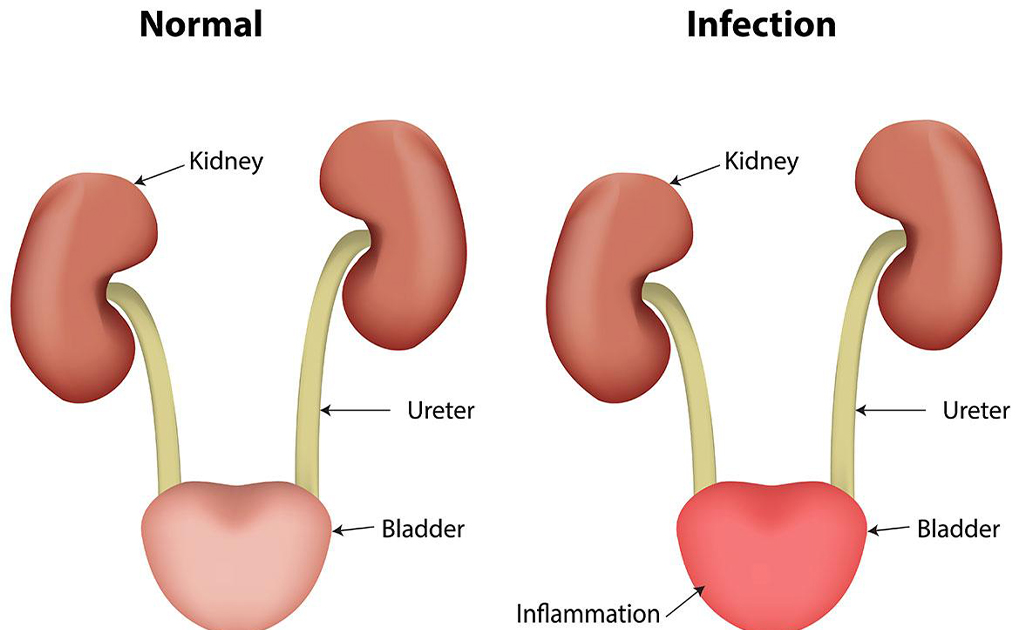

প্রস্রাবে জ্বালাপোড়ার কারণ ও ঘরোয়া প্রতিকারের ৫টি উপায়

0 SHARES Share Tweet আমরা সকলেই প্রস্রাবে জ্বালাপোড়া বা ইউরিন ইনফেকশনের সাথে কমবেশী পরিচিত। প্রায় প্রত্যেকটি ঘরেই প্রস্র...